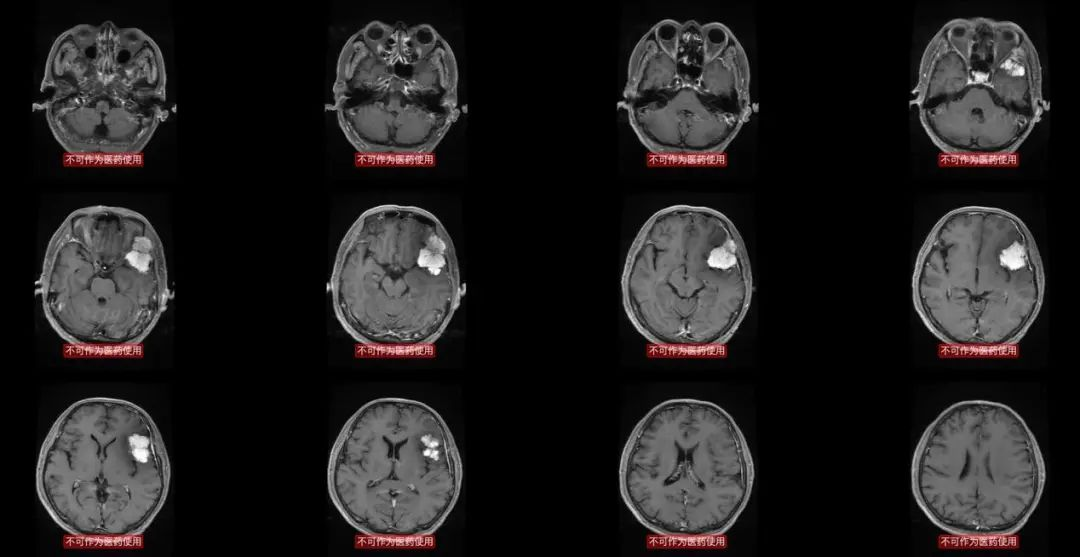

这是术前的磁共振,肿瘤与侧裂静脉的关系比较密切,需要关注。

2016-9-7手术,术中有一个颞叶的静脉比较粗大,开始一直保留,最后阶段,出血,后来电凝止血后,术后一直不放心,病人清醒,但是头痛,一直担心会不会出血?静脉瘀血?

由于中华医学会神经外科年会在兰州举行,我9月9日还有大会发言,准备了9月8日去兰州的航班。所以术后当日晚上复查头颅CT:有少量渗血,不需要再次手术。

这是12月21日复查的头颅MR,肿瘤没有复发征象,全切,也没有明显脑水肿。